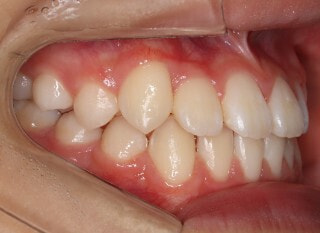

小児期の第二段階

終了時